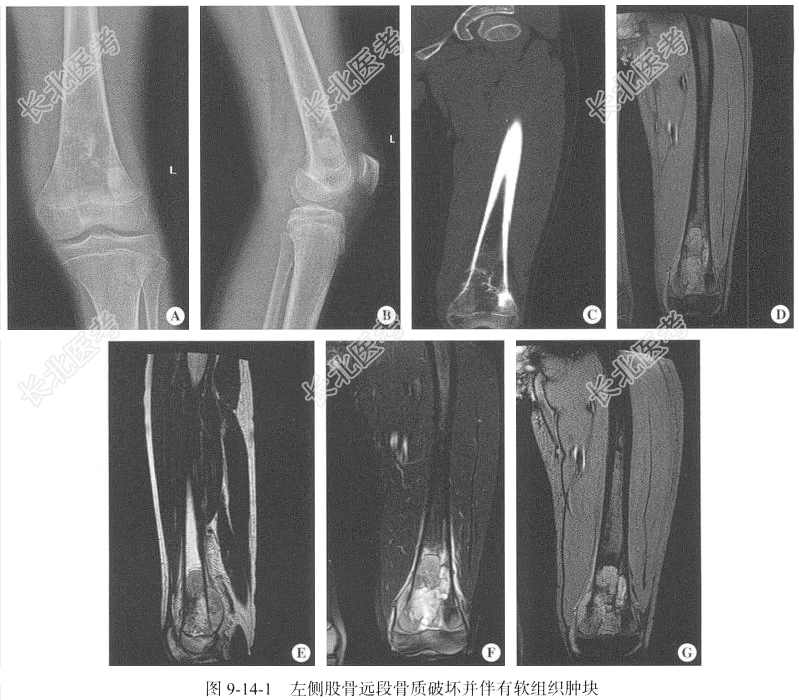

- [材料题] 【临床病史】女性,8岁。于20天前无明显诱因出现左侧膝关节周围疼痛不适,为钝痛,休息时缓解,活动时加重,以夜间痛为主,膝关节活动稍受限。

【专科查体】患儿左膝关节周围疼痛不适,活动受限。患处皮温未升高,左侧膝关节周围软组织肿胀,未见化脓及瘘道形成。

【影像检查】左侧膝关节DR正侧位;左侧股骨CT扫描,层厚为3mm,层间隔3mm,并进行CT冠状位重建;右侧股骨MRI扫描,包括T₁WI、T₂WI及T₂WI脂肪抑制序列,扫描层厚为5mm,层间隔5mm;辅以冠状位T₂WI、矢状位T₂WI脂肪抑制序列、冠状位增强扫描。

【影像图片】见图9-14-1。

【手术所见】逐层切开皮肤、皮下组织及深筋膜后,可见灰红色质硬病变组织,留取标本送检。

【病理所见】左侧股骨远端病变组织,不整组织一堆,大小为1.5cm×1.5cm×0.2cm,呈灰红色,质硬,脱钙(图9-14-2)。

【病理诊断】骨肉瘤。